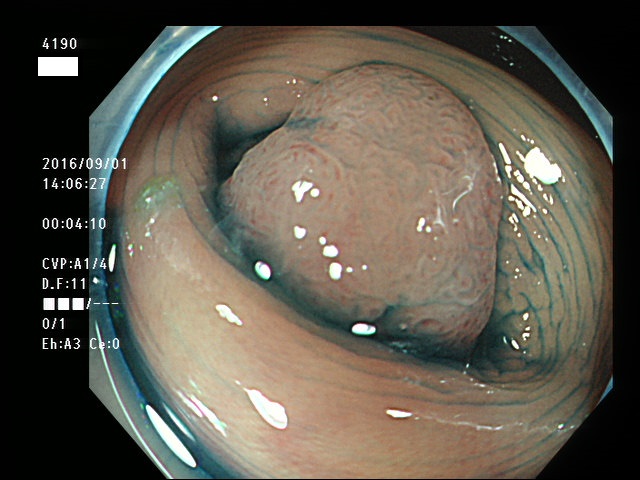

回盲弁(小腸と盲腸の境界)や、憩室の中、炎症で腫れた部位などは複雑に凸凹しており、ここに微小な病変、平坦な病変があると認識が困難になり見落としの危険が高くなります

| 炎症性の隆起(腫れ)の上に発生した腺腫 | 回盲弁上に発生した腺腫(高度異型) |